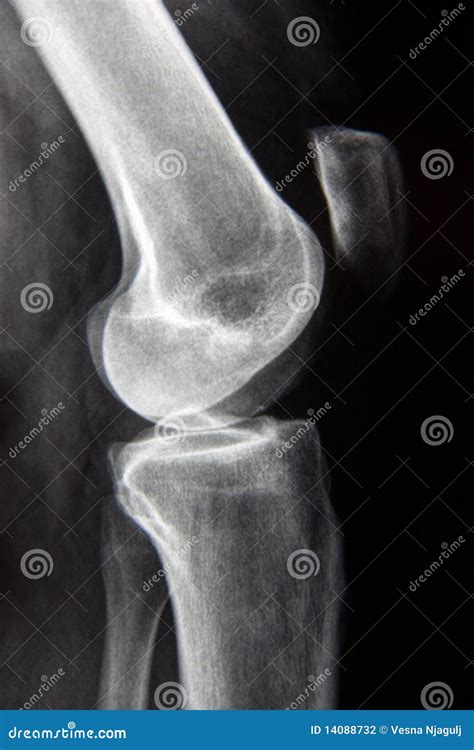

A Lateral Knee Xray is a type of radiographic imaging that captures a side view of the knee joint. This view is essential for evaluating the alignment of the bones, the condition of the joint spaces, and the presence of any abnormalities such as fractures, dislocations, or arthritis. The lateral view complements other views, such as the anteroposterior (AP) and oblique views, to provide a comprehensive assessment of the knee.

• Diagnosing Fractures: A lateral view can help identify fractures in the patella (kneecap), femur (thighbone), or tibia (shinbone).

• Evaluating Joint Spaces: It provides a clear view of the joint spaces, which can indicate the presence of arthritis or other degenerative conditions.

• Assessing Alignment: The lateral view helps assess the alignment of the knee joint, which is crucial for diagnosing conditions like patellar dislocation or tibial plateau fractures.

• Detecting Soft Tissue Injuries: While X-rays primarily show bone structures, a lateral view can sometimes reveal soft tissue injuries, such as ligament tears or meniscal damage, by showing indirect signs like joint effusion (swelling).